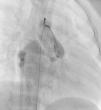

Os motivos de referência mais frequentes foram sopro e/ou cansaço. Todas as fístulas eram de origem congénita. Cinco doentes (42%) tinham patologia cardíaca concomitante: atrésia da pulmonar com septo interventricular intacto (1), canal arterial persistente (1), comunicação interauricular ostium secundum (1), estenose aórtica em válvula aórtica biscúspide (1), estenose pulmonar crítica operada no período neonatal (1). Foram realizadas angiografias selectivas para delinear a anatomia da(s) fístula(s). A embolização foi feita na porção mais distal da fístula, poupando todos os ramos colaterais. Num doente foi realizada uma ansa arteriovenosa através da fístula, com embolização da porção terminal da fístula a partir da aurícula direita. Os doentes foram heparinizados (100 U.I./kg na criança e 5000 U.I. no adulto) e foi feito o controlo posterior através do valor de ACT. Três dos doentes apresentavam duas fístulas e os restantes comunicações fistulosas isoladas. As fístulas eram todas hemodinamicamente significativas e tinham origem no território da coronária direita (n=10), da coronária esquerda (n=3) e da circunflexa (n=2) e drenavam para o ventrículo direito (n=5), artéria pulmonar (n=6), aurícula direita (n=2), seio coronário (n=1) e ventrículo esquerdo (n=1). O material de embolização incluiu 15 coils standard em 3 doentes, 1 coil Jackson® num doente (Figuras 1–3), 27 microcoils em 11 doentes (18 microcoils simples em 7 doentes e 9 microcoils GDC em 4 doentes) e um dispositivo Amplatzer®Duct Occluder num doente (Figuras 4–7). Merece um destaque especial os microcoils GDC, simples ou complexos, que são dispositivos de libertação controlada por electrólise, o que permite que o procedimento seja reversível até à fase final da libertação, após se confirmar a boa posição do dispositivo. Num doente foi testado um plug cardíaco Amplatzer® que não foi libertado por não ser adequado à lesão.

A abordagem clássica da fístula coronária é o encerramento cirúrgico. Em 1997, Mavroudis et al apresentou uma análise sobre resultados cirúrgicos de encerramento de fístulas coronárias em 17 doentes com idades compreendidas entre as seis semanas e os 16,5 anos (idade média 5,5 anos) e tratados entre 1968 e 1996, concluindo que o encerramento cirúrgico de fístulas coronárias foi 100% eficaz e sem mortalidade naquela série, pelo que deve ser o tratamento de eleição nestas situações, devendo o encerramento percutâneo ficar reservado para apenas uma pequena população seleccionada11. Contudo, já em 1991, tinha sido descrito o encerramento percutâneo de sete fístulas coronárias em doentes com idades compreendidas entre os dois e os 67 anos (idade média de 17 anos), que decorreu com sucesso em seis das sete fístulas encerradas e sem complicações durante um tempo de seguimento de quatro meses a quatro anos12. Neste artigo, os autores chamam a atenção para a vantagem do encerramento percutâneo com a possibilidade de se evidenciarem fístulas adicionais após o encerramento da(s) fístula(s) de maiores dimensões apenas visível(is) no encerramento percutâneo. Apesar de tecnicamente mais difícil, fístulas de grandes dimensões a drenarem para a aurícula direita ou para o ventrículo direito podem ser encerradas por via venosa com dispositivos como Amplatzer®Duct Occluder ou plugs, com monitorização do posicionamento adequado do dispositivo através de injecções selectivas retrógradas na artéria coronária, como descrito em 2000 por Pedra et al5 e realizado no nosso caso 9 (Fig. 1 a 4).